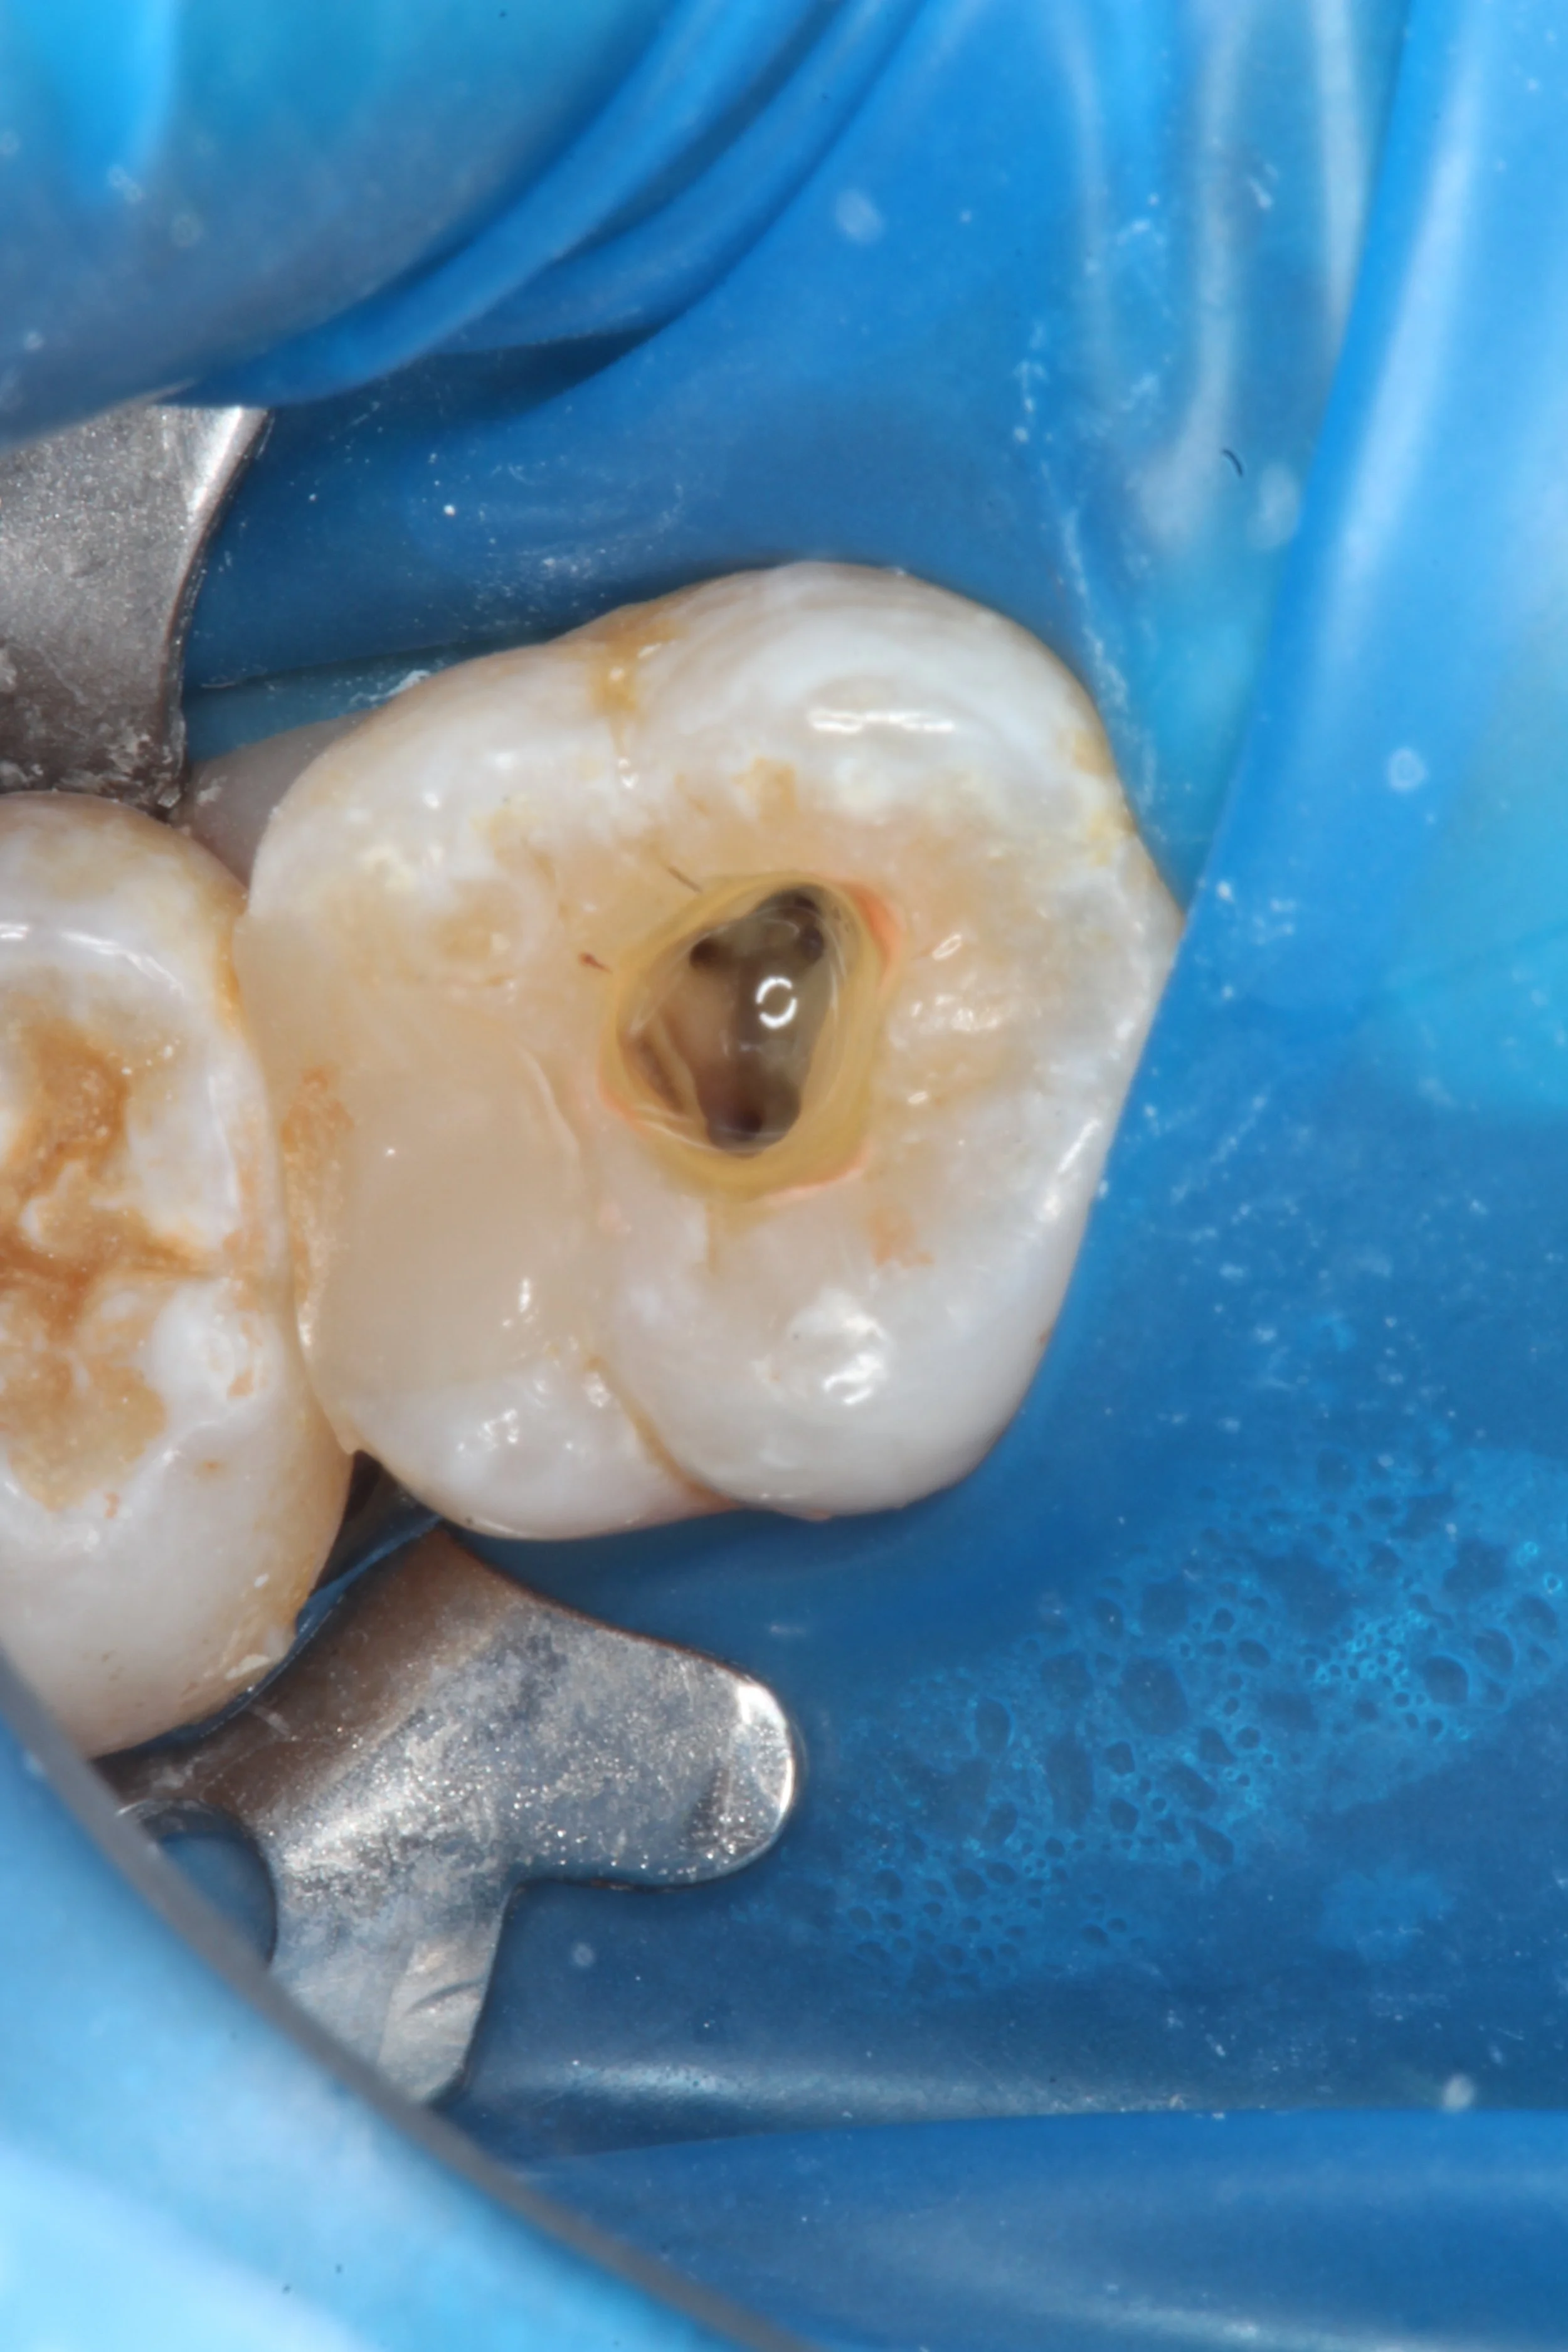

Endodontics